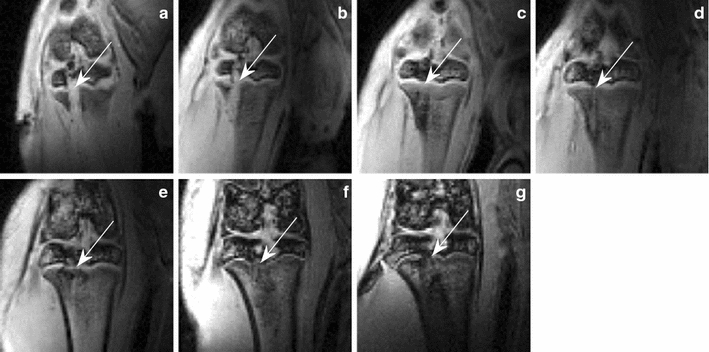

摘要:骨桥形成后发生骨骺病变,如果没有逆转可导致生长停滞。关于这种形成的基本机制的先前研究使用组织学方法。因此,本研究旨在利用动态增强MRI应用微创方法。材料和方法:应用参考区域模型对一组动物模型进行纵向研究评估了与微血管系统相关的功能参数的变化。用三维高分辨率MRI研究受伤的物理形态发展。结果:药动学参数的评价显示转移系数在术后7天首次升高,术后42天最高。对互补数据的分析显示,第一次上升与微血管增生有关,而最大值与骨重塑有关。结论:DCE-MRI的药代动力学分析显示在愈合过程中微血管的增生是骨桥形成的标志。因此,MRI可识别细节,对高侵入性方法进行分析。关键词:造影剂 动物模型 长骨体生长部简介:过早骨骺骨桥形成可以由各种生长毒性包括外伤、感染、辐射、缺血、热损伤、布朗特病、类固醇的使用。一般包括金属植入术医源性损伤是一个骺板骨桥形成的主要原因。骨桥在小的时候可能是可逆的,但也可以触发全部或部分由于过早骨骺闭合不完全分解,因此可能导致全部或部分生长阻滞引起骨长度差异,轴线偏差或关节畸形。临床上,通过X光来检查,这些检查要么常规地记录骨折愈合,要么开始于创伤后骨长度改变或畸形患者。然后,MRI用于记录桥的全尺寸,有助于进一步的治疗。严重的骨骺骨桥改变了正常的骨骼纵向生长,需要手术切除和填补损害自体脂肪组织作为补救措施,或实施对侧固定术或截骨矫正术。此外,干细胞治疗和自体培养的骺板软骨细胞移植是最近研究的新的治疗选择。相比之下,较小的骨桥通常在生长过程中保持隐蔽和消失,而不会影响正常的纵向生长。在各种实验动物模型通过组织学和MR I证实骺板骨桥形成。在骺板骨桥形成之前出现微血管增生。随着入侵血管从周围骨骺和干骺端的骨基质骨祖细胞进入骨骺的病变部位,归因于沉积骨,最终导致骨桥形成。在骺板损伤部位骨桥发展前通过检测血管生成因子表达的增加进一步支持了增加的血液供应是损伤部位与骨骺骨桥血管和微血管侵犯骨组织的发展的基础。然而诱导新生血管形成,紧接着是骺板骨桥形成的潜在病理机制还有待研究。在骨骺病变血供增加检测可以识别早期的骨桥形成,而血管生成因子表达的测定需要组织样本,磁共振成像是潜在的能够提供这种信息的非侵入性方法。动态对比增强磁共振成像(MRI)对微血管系统功能参数敏感。因此它是一种工具来描述血管和微血管并被广泛用于肿瘤的分析。药动学参数识别的典型模型需要组织造影剂(CA)浓度时间信息和血管内造影剂浓度-动脉输入功能(AIF)。采集同一视场(FOV)的骨骺损伤是非常具有挑战性的,确定信号噪声比(SNR)、对比度行为和时间或空间分辨率的界限。本研究的目的是探讨与骨桥形成相关骨骺病变微血管系统药动学参数。这些参数通常在代谢增强的组织中增加,与表面渗透性产物、血流量和血容量有关。这些参数的研究应该支持这一假设,即微血管系统的改变是骨桥形成的基本机制,可以为早期识别这一发展提供定量的措施。方法:动物:77只雄性SD大鼠,体重约100g,一月龄,全身麻醉后进行单侧骨骺损伤。通过胫骨近端骨骺,经正中切口髌腱近端进入钻成1.2mm直径的损伤。术后第0、1、3、7、14、28、和80天时每次处死6只动物取样用于qRT-PCR分析。在1, 3, 7、14, 28, 42和82天各处死五只动物进行组织学观察。在相同的7个时间点用麻醉的动物进行MR测量。在损伤后第一个月内,在短时间内设置研究时间点,以密切注视骨桥的形成和微血管系统的变化。42和82天的长期时间点被确定为进一步的增长观察点,观察骨重塑和检测潜在的骨桥消失。MR测量:用38mT/ m梯度强度的临床3 T扫描仪进行DCE-MRI和形态学的磁共振成像。为了提高图像质量,特别使用直径为18毫米的表面接收线圈。使用如图1所示的布置,可以在整个研究期间保持对大鼠膝盖的最小距离,从而最大限度地提高信噪比。动物被俯卧,膝盖放在线圈的中心。动物放在半圆形动物床提供稳定和可重复的装配。如上所述,在第1, 3, 7、14, 28, 42和第82天进行测量。用高分辨率的三维FLASH序列对被调查区域的形态变化进行成像。组织学:为获得的血管形成互补的信息对近端骨骺,骨骺与干骺端的骨标本进行免疫组织化学分析。组织学标本固定在甲醇(100%)24小时后采用乙二胺四乙酸脱钙(pH 7)两周。在甲醇(100%)中进一步固定12小时,样品在PBS-蔗糖5%溶液中冲洗,用组织冷冻介质覆盖,切成7毫米厚的薄片。可视化的骨骺缺损采用IV型胶原染色血管形成,如IV型胶原是一种血管基底膜蛋白,染色血管呈红色/棕色。结果:扫描显示(用箭头标注),一个有代表性的动物的所有7个时间点的损伤区的物理变化和骨桥的形成,钻后第1天和3天,钻痕造成的骨骺中断清晰可见。第7天骨骺中断消失。第14天时可见最早的骨桥,逐渐被定义为一个更大的低信号中断,这些干扰一直存在直到研究结束。信噪比在两周后有明显的下降:骨骼肌在前14天平均信噪比为82,随后为76。对于骨骺,信噪比从72下降到36的平均水平。组织学研究显示骨骺缺陷区微血管的生长。图显示IV型胶原染色组织切片1, 3, 7天,14, 28, 42和82的骨骺损伤。第1天的染色显示无血管形成。术后第3天和第7天,染色清楚显示毛细血管的存在。两周后,能在骨缺损部位观察到第一骨小梁(IV型胶原阴性,用箭头标注)。相比第3和第7天,胶原蛋白IV阳性血管似乎更结构化。在第42天,缺损区域充满了由血管包围的片状骨碎片。术后第82天,与第42天相比,IV型胶原阳性血管数量减少。结论:MR测量不仅记录骨桥的形成,而且还提供了损伤区组织发育和微血管增生的定量信息。在形态学图像可见性之前,分析DCE数据分析这可能有助于预防儿童的生长障碍,允许早期进行治疗干预。然而,这一发现仍需要在人类研究中加以验证。